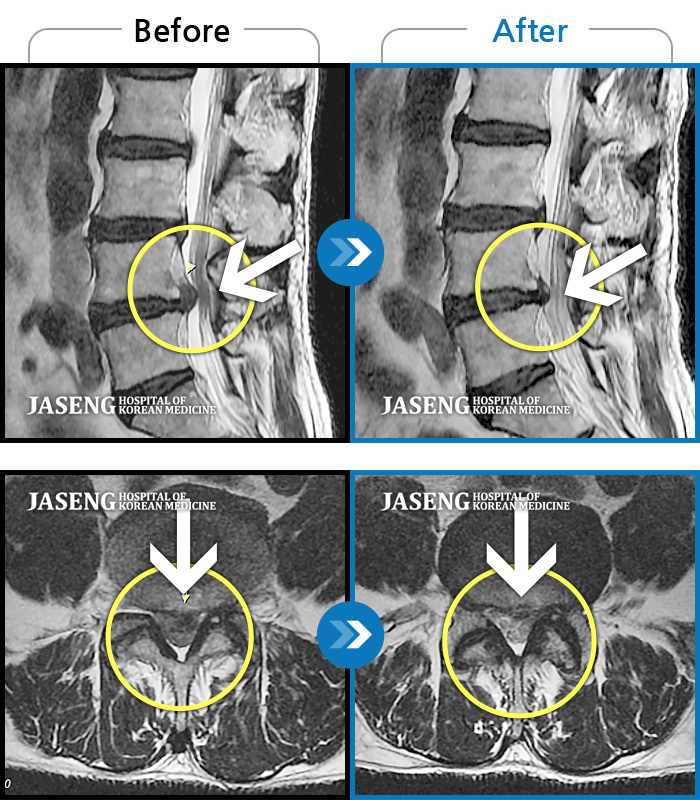

Before

After

환자에게 사전 동의를 받아 동일 조건에서 촬영되었습니다.

개인에 따라 치료 후 부작용이 발생할 수 있으니 의료진과 상담 후 치료를 진행하시기 바랍니다.

허리디스크로 연골이 거의 없다고 진단 받음

요통과 좌측 하지방사통으로 내원